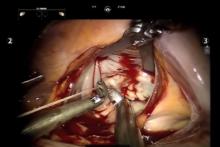

Robotic Repair of Mitral Endocarditis With Preoperative Neurologic Embolic Events [1]

This video shows a complex mitral valve repair performed for active endocarditis with persistent bacteremia, fevers, and embolic neurologic events. The patient underwent a robotic-assisted repair with the excision of several vegetations, and then subsequent leaflet plasty and pericardial leaflet patch repair. The patient had an uneventful post-operative recovery with no recurrent neurologic events and resolution of the endocarditis.